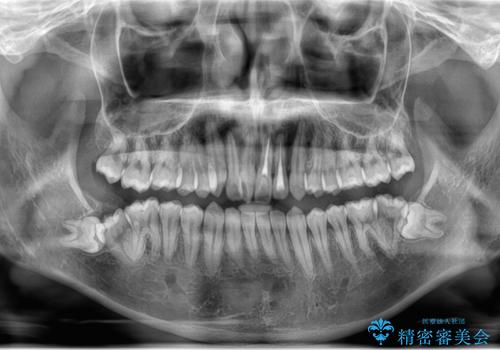

- 右上下親知らずを抜きたいとの事で来院。

レントゲンを確認したとこと完全埋伏歯でした。

CTで神経の位置などを確認し、抜歯術を行いました。